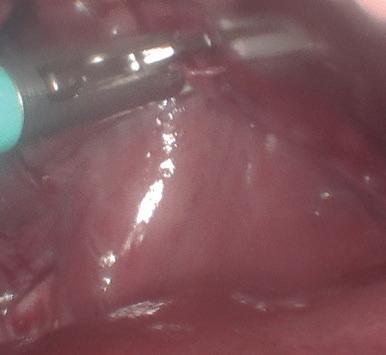

Se presenta el caso de una gata sometida a craneotomía supratemporal para exéresis de un menigioma, en la que se realizó un mantenimiento anestésico intravenoso para mantener una mayor estabilidad hemodinámica durante la cirugía.

Maine Coon, hembra castrada de 8 años, 3,5 kg y condición corporal 5/9, diagnosticada mediante resonancia magnética de una lesión extradural que afectaba a los lóbulos parietal, temporal y occipital (posiblemente meningioma) y que le producía un cuadro de circling, que en el momento de la anestesia estaba controlado gracias al tratamiento con dexametasona 0,15 mg/ kg/24 h. Como otros antecedentes clínicos, la paciente presentaba barro biliar, iniciándose el tratamiento con ácido ursodesoxicólico.